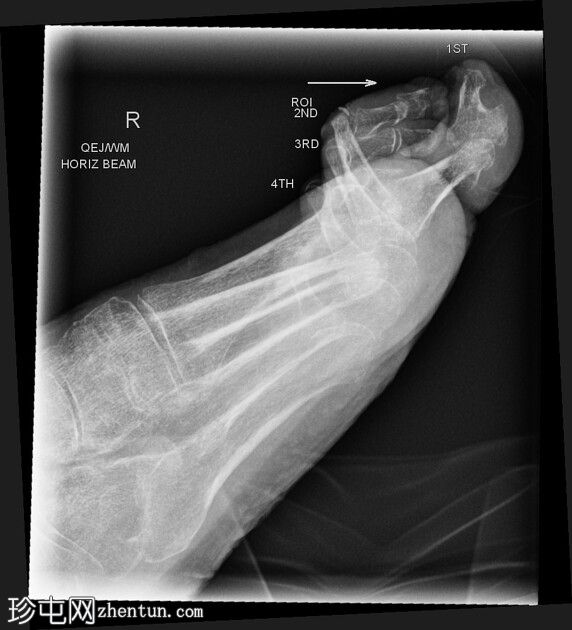

正位

侧位

第二至第五趾跖趾关节明显过伸,近端趾间关节屈曲,符合爪状趾畸形。部分远端趾间关节屈曲程度不及其他关节。

侧位片显示第二近节趾骨头背侧皮质透亮,符合骨髓炎表现。